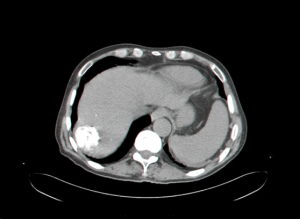

- CT המראה נגעים בכבד. בשאתות קטנות הרגישות של ה- CT ו- US זהה ולכן US משמש לסיקור באוכלוסיות בסיכון גבוה. בעזרת ה- CT ניתן לאתר גם נגעים מחוץ לכבד. ה- CT הספירלי מאפשר לנו לבצע שחזור כלי דם ולהדגים את עושר כלי הדם העוטפים את השאת. ההדגמה ב- CT היא תלת פאזית

- בדרך כלל אין צורך בביופסיה מחטית של הנגע בתנאי שניתן לראות ב- CT מאפיינים קלאסיים ל- HCC. כיוון שה- HCC היא שאת מאוד וסקולרית הרי שהיא "נצבעת" מהר וחזק בשלב ההזרקה ויש שטיפה מהירה בשלב הפורטלי המאוחר (תצלום 30.10-33.10).

| תצלום 30.10: שאת בכבד הנראית ב- CT. מימין HCC הבולטת על פני הכבד. משמאל פגם מילוי בכבד כביטוי לשאת בכבד (החץ מצביע על השאת). | |

|---|---|